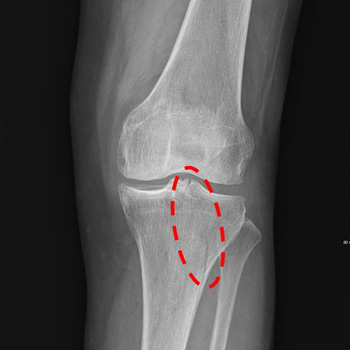

X-ray result

▲ Before prayer: patella fracture with articular surface